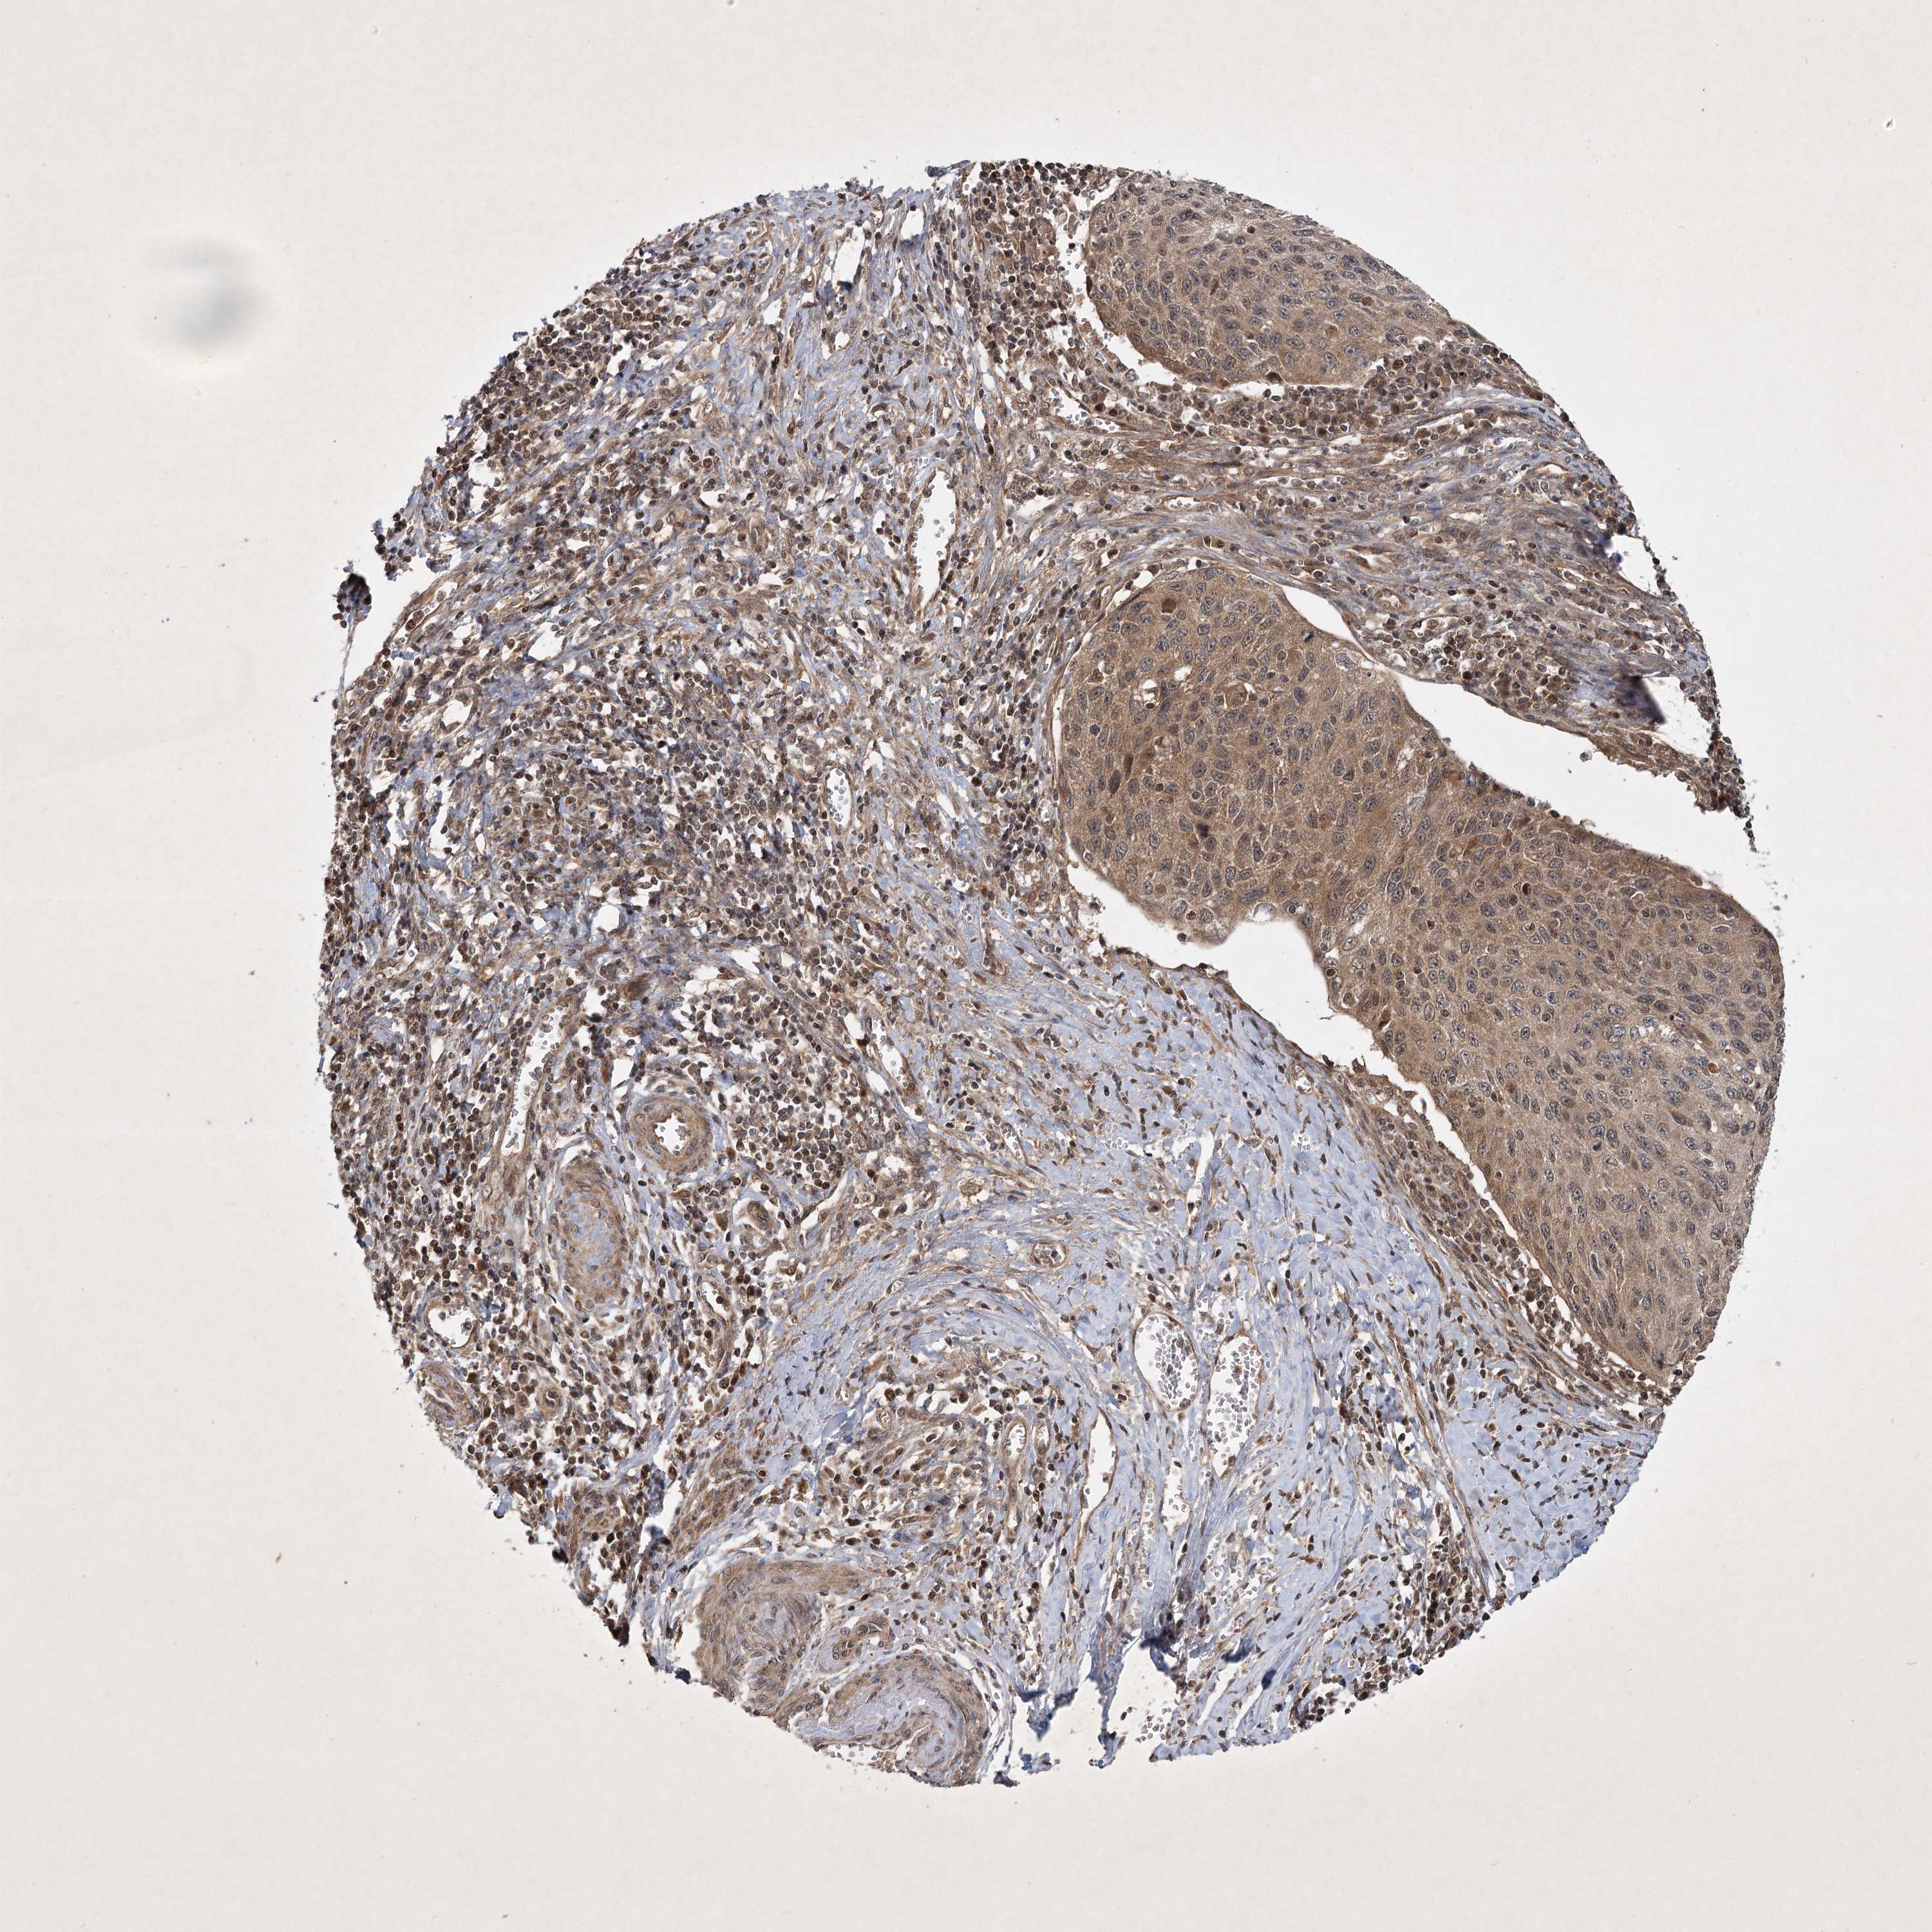

CERVICAL CANCER - Protein expressioni

A mouse-over function shows sample information and annotation data. Click on an image to view it in a full screen mode. Samples can be filtered based on level of antibody staining by selecting one or several of the following categories: high, medium, low and not detected. The assay and annotation is described here.

Note that samples used for immunohistochemistry by the Human Protein Atlas do not correspond to samples in the TCGA dataset.

Antibody stainingi

Antibody staining in the annotated cell types in the current human tissue is reported as not detected, low, medium, or high, based on conventional immunohistochemistry profiling in selected tissues. This score is based on the combination of the staining intensity and fraction of stained cells.

Each image is clickable and will lead to virtual microscopy that enables deeper exploration of all samples and also displays staining intensity scores, fraction scores and subcellular localization as well as patient and tissue information for each sample.

Antibody CAB033861

Staining

High

Medium

Low

Not detected

Intensity

Strong

Moderate

Weak

Negative

Quantity

>75%

75%-25%

<25%

None

Location

Nuclear

Cytoplasmic/membranous

Cytoplasmic/membranous,nuclear

Squamous cell carcinoma, NOS

Adenocarcinoma, NOS